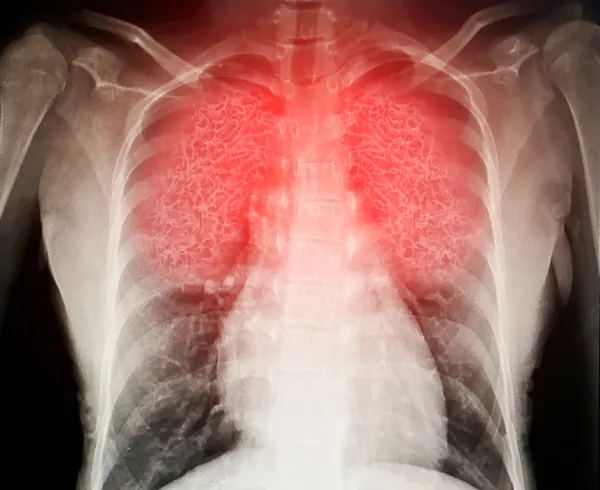

AKCİĞER HASARINI 14 KAT ARTIRIYOR

Prof. Dr. Vefik Arıca, "Şimdiye kadar olan bilimsel verilerle koronavirüs enfeksiyonuna yakalanan kişilerin eğer sigara içimi var ise akciğerde oluşabilecek hasarı 14 kat daha fazla arttırabileceğini yani şiddetini arttırdığını biliyorduk. Yapılan araştırmalara göre, İngiltere mutasyonu ile sigara içilmesi arasındaki yakın ilişki ve sigara içilmesinin İngiltere mutasyonlu koronavirüse duyarlılığı arttırıyor." dedi.